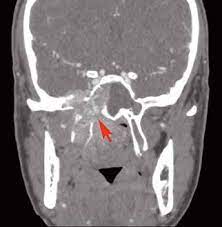

Это доброкачественное новообразование, располагающееся в носоглотке детей и подростков. Характерная дислокация патологии – задняя часть носа, где находятся аденоиды. Ангиофибромы быстро увеличиваются в размерах, отличаются агрессивностью. Прогрессирующая опухоль склонна к разрушениям окружающей костной структуры. Неоплазия распространяется на соседние области: черепное основание, черепную полость, глазные орбиты, и склонна к кровоточивости, что делает ее особенно опасной. Ювенильная назофарингеальная ангиофиброма (ЮНА) представляет собой рыхлую опухолевую массу, содержащую переплетение кровеносных сосудов.

- Инструментальные, визуализирующие методы исследования – МРТ, КТ, ангиография, рентген, эпифарингоскопия.